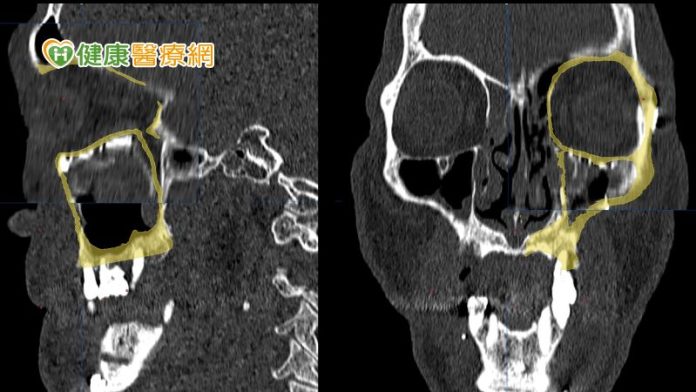

在術前醫師會先透過電腦斷層模擬病人顏面骨骼,並設計出貼近病人原始骨頭構造的立體結構,再利用3D列印技術客製化眼眶骨及顴骨模型,預先調整眼底鈦合金骨板的形狀。黃子桓醫師表示,這不僅能精確地重建,也可以節省手術時間,並提升成功率避免二次手術的可能。

不過,黃子桓醫師提到,如果是已在錯誤位置癒合的顏面骨骨折,重建手術會更為複雜,切斷已癒合的骨塊後,要在立體空間中將骨塊移動到理想位置其實並不容易,在沒有導航的幫助下,手術的不確定性會很高,若術中同步利用導航輔助定位,將能大幅提高精確性。

因此,醫療團隊在術前為李先生模擬、設計精確的復位計畫後,術中也同步利用導航系統協助定位,將錯位的骨塊逐步復位至理想的位置。黃子桓醫師表示,李先生在經過手術後,恢復良好的咬合關係及左右顏面對稱性,住院一週便順利出院。